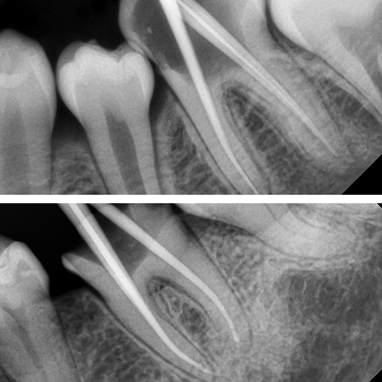

Nyeri akibat gigi berlubang parah dapat segera teratasi, bahkan sejak kunjungan pertama.

Dengan penanganan dokter gigi berpengalaman di Dharmawangsa Dental Studio, perawatan saluran akar dilakukan dengan teknologi modern sehingga nyeri hilang lebih cepat dan pasien merasa nyaman.